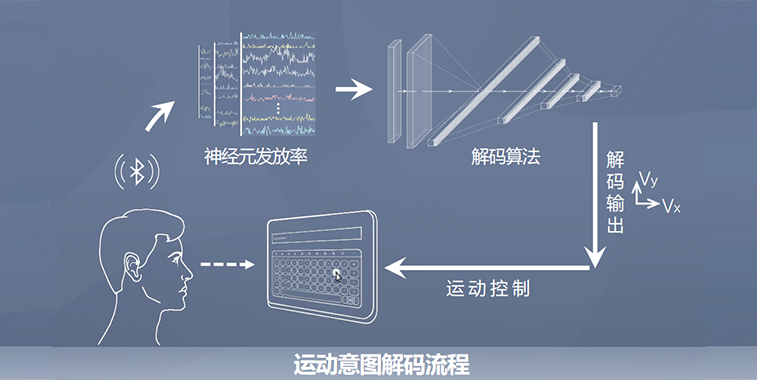

二维运动轨迹解码,平均轨迹误差毫米级别;纯脑控实验正确率接近100%。

高通道解码算法耗时~ 1 ms,相比传统算法提升100 倍;纯脑控试验中运动想象范式完成时间比手部自然运动快37%。

适配多种范式,支持不同临床场景;模型支持跨天、 跨个体快速适配。